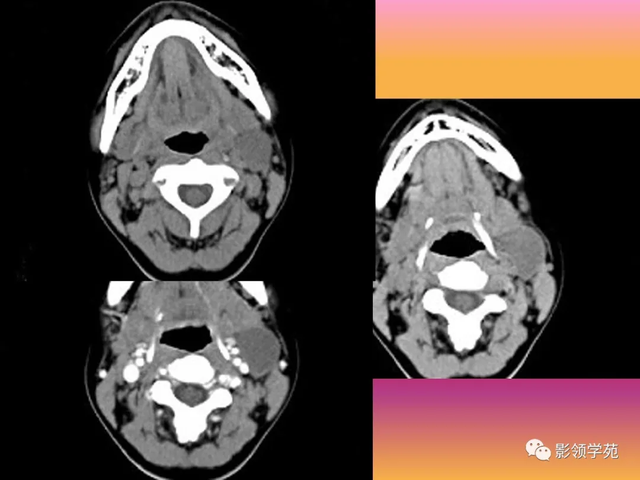

病例3:男性,68岁,因“发现右耳垂下肿物30余年”:

病理:腺淋巴瘤

病例4:男性,81岁,因发现右耳下肿物10年余,举行 性增大2年: